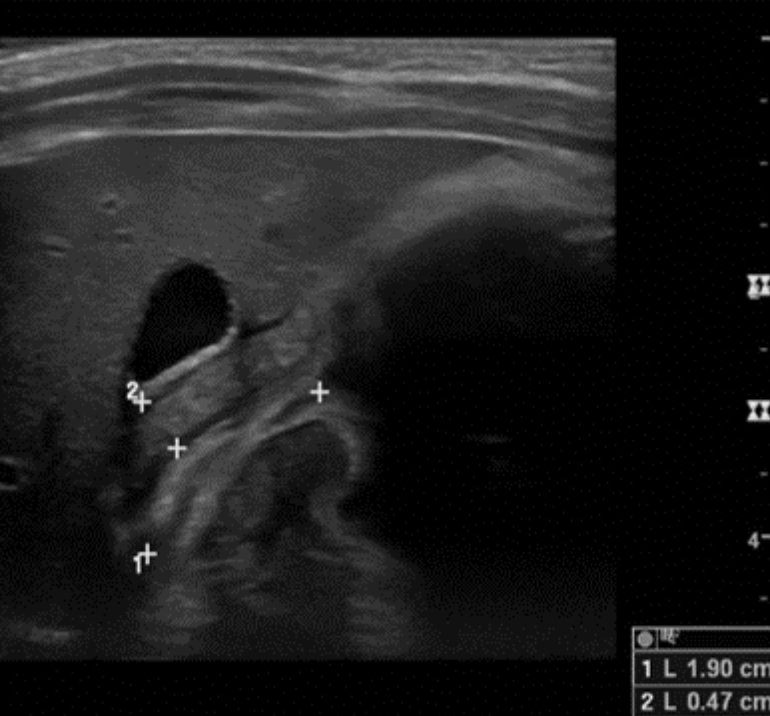

Diagnosis of HPS is most commonly made by ultrasound. An ultrasound is considered positive for HPS when the pylorus is visualized to have a thickness of greater than 3 mm and a length of greater than 14 mm - this may be recalled using the mnemonic of “pi” = 3.14. Infants with suspected HPS should also have serum electrolytes and bilirubin drawn to evaluate for possible metabolic derangements.

Figure: Ultrasound image demonstrating HPS. Image courtesy of Dr. Stephanie Leung. Used with permission.

- When interpreting an ultrasound for HPS, remember "pi = 3.14." A pylorus visualized to be greater than 3 mm in thickness and 14 mm in length are consistent with HPS.

The patient has an ultrasound in which the pylorus measures 4.7 mm in thickness and 19 mm in length. Serum chemistry is significant for potassium 2.7 mEq/L, chloride 92 mmol/L, and bicarbonate 31 mmol/L. Pediatric Surgery is consulted, and the patient is admitted to their service for laparoscopic pyloromyotomy following correction of electrolyte derangements with fluid resuscitation. Following the surgery, the patient is discharged as a happy baby who is tolerating feeds well.